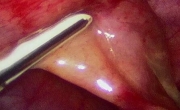

• 2. 使用环状接头

1.jpg

有些制造商提供一个消毒的环状接头,可以放置在摄影机和内视镜之间。理论上,这些环状接头非常实用,因为它们可以使医师改变接到摄影机上的内视镜。实际上,从内视镜移开镜头2 cm 会缩小视野,减少亮度和损失影像质量。